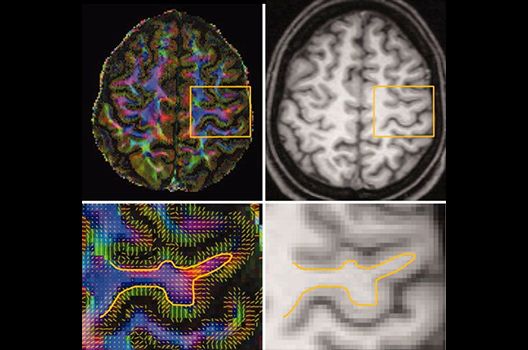

Die Magnetresonanztomographie (MRT) ist ein Verfahren, bei dem durch magnetische Kräfte Bilder des Körperinneren angefertigt werden. In der Neuroradiologie können manchmal kleinste Veränderungen schwere Folgen haben; daher forschen wir an der Entwicklung hochauflösender MRT-Sequenzen, mit denen diese Prozesse und auch einzelne Nervenfaserbahnen sichtbar gemacht werden können. Darüber hinaus sind bei vielen Erkrankungen des Gehirns die Blutgefäße betroffen. Daher arbeiten wir an der Neu- und Weiterentwicklung von MRT-Sequenzen zur Darstellung der Blutgefäße und zur Blutflussanalyse (sog. „Angio-MRT“). Einen besonderen Forschungsschwerpunkt unserer Klinik stellen die MR-Protonenspektroskopie und die funktionelle MRT dar, mit denen die Analyse einzelner chemischer Substanzen im Hirngewebe oder die Darstellung ausgewählter Hirnfunktionen möglich ist.